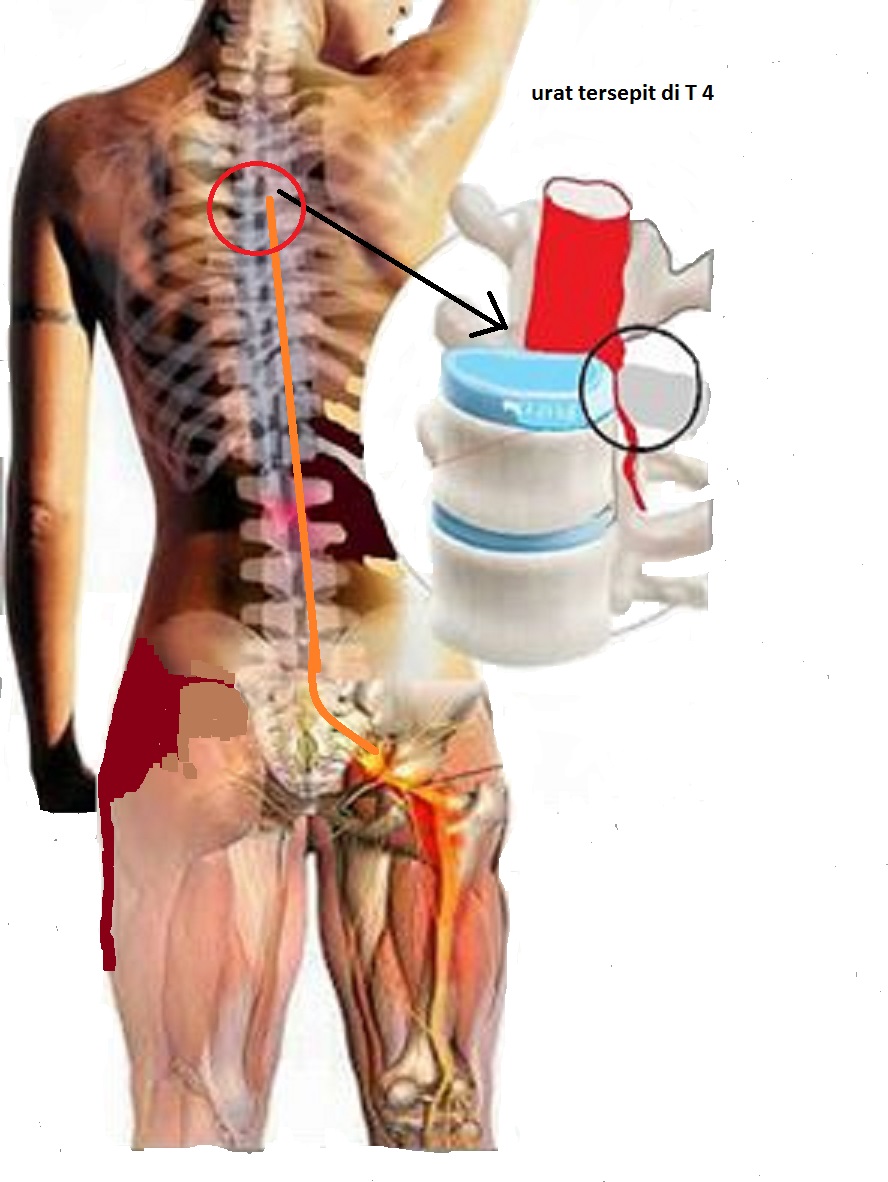

Prissna Wellness & Therapy Centre (Pusat Rawatan PRISSNA): SAKIT PINGGANG ,SAKIT LUTUT , SAKIT URAT PUNGUNG DAN TULANG BENGKOK

Prissna Wellness & Therapy Centre (Pusat Rawatan PRISSNA): SAKIT PINGGANG ,SAKIT LUTUT , SAKIT URAT PUNGUNG DAN TULANG BENGKOK